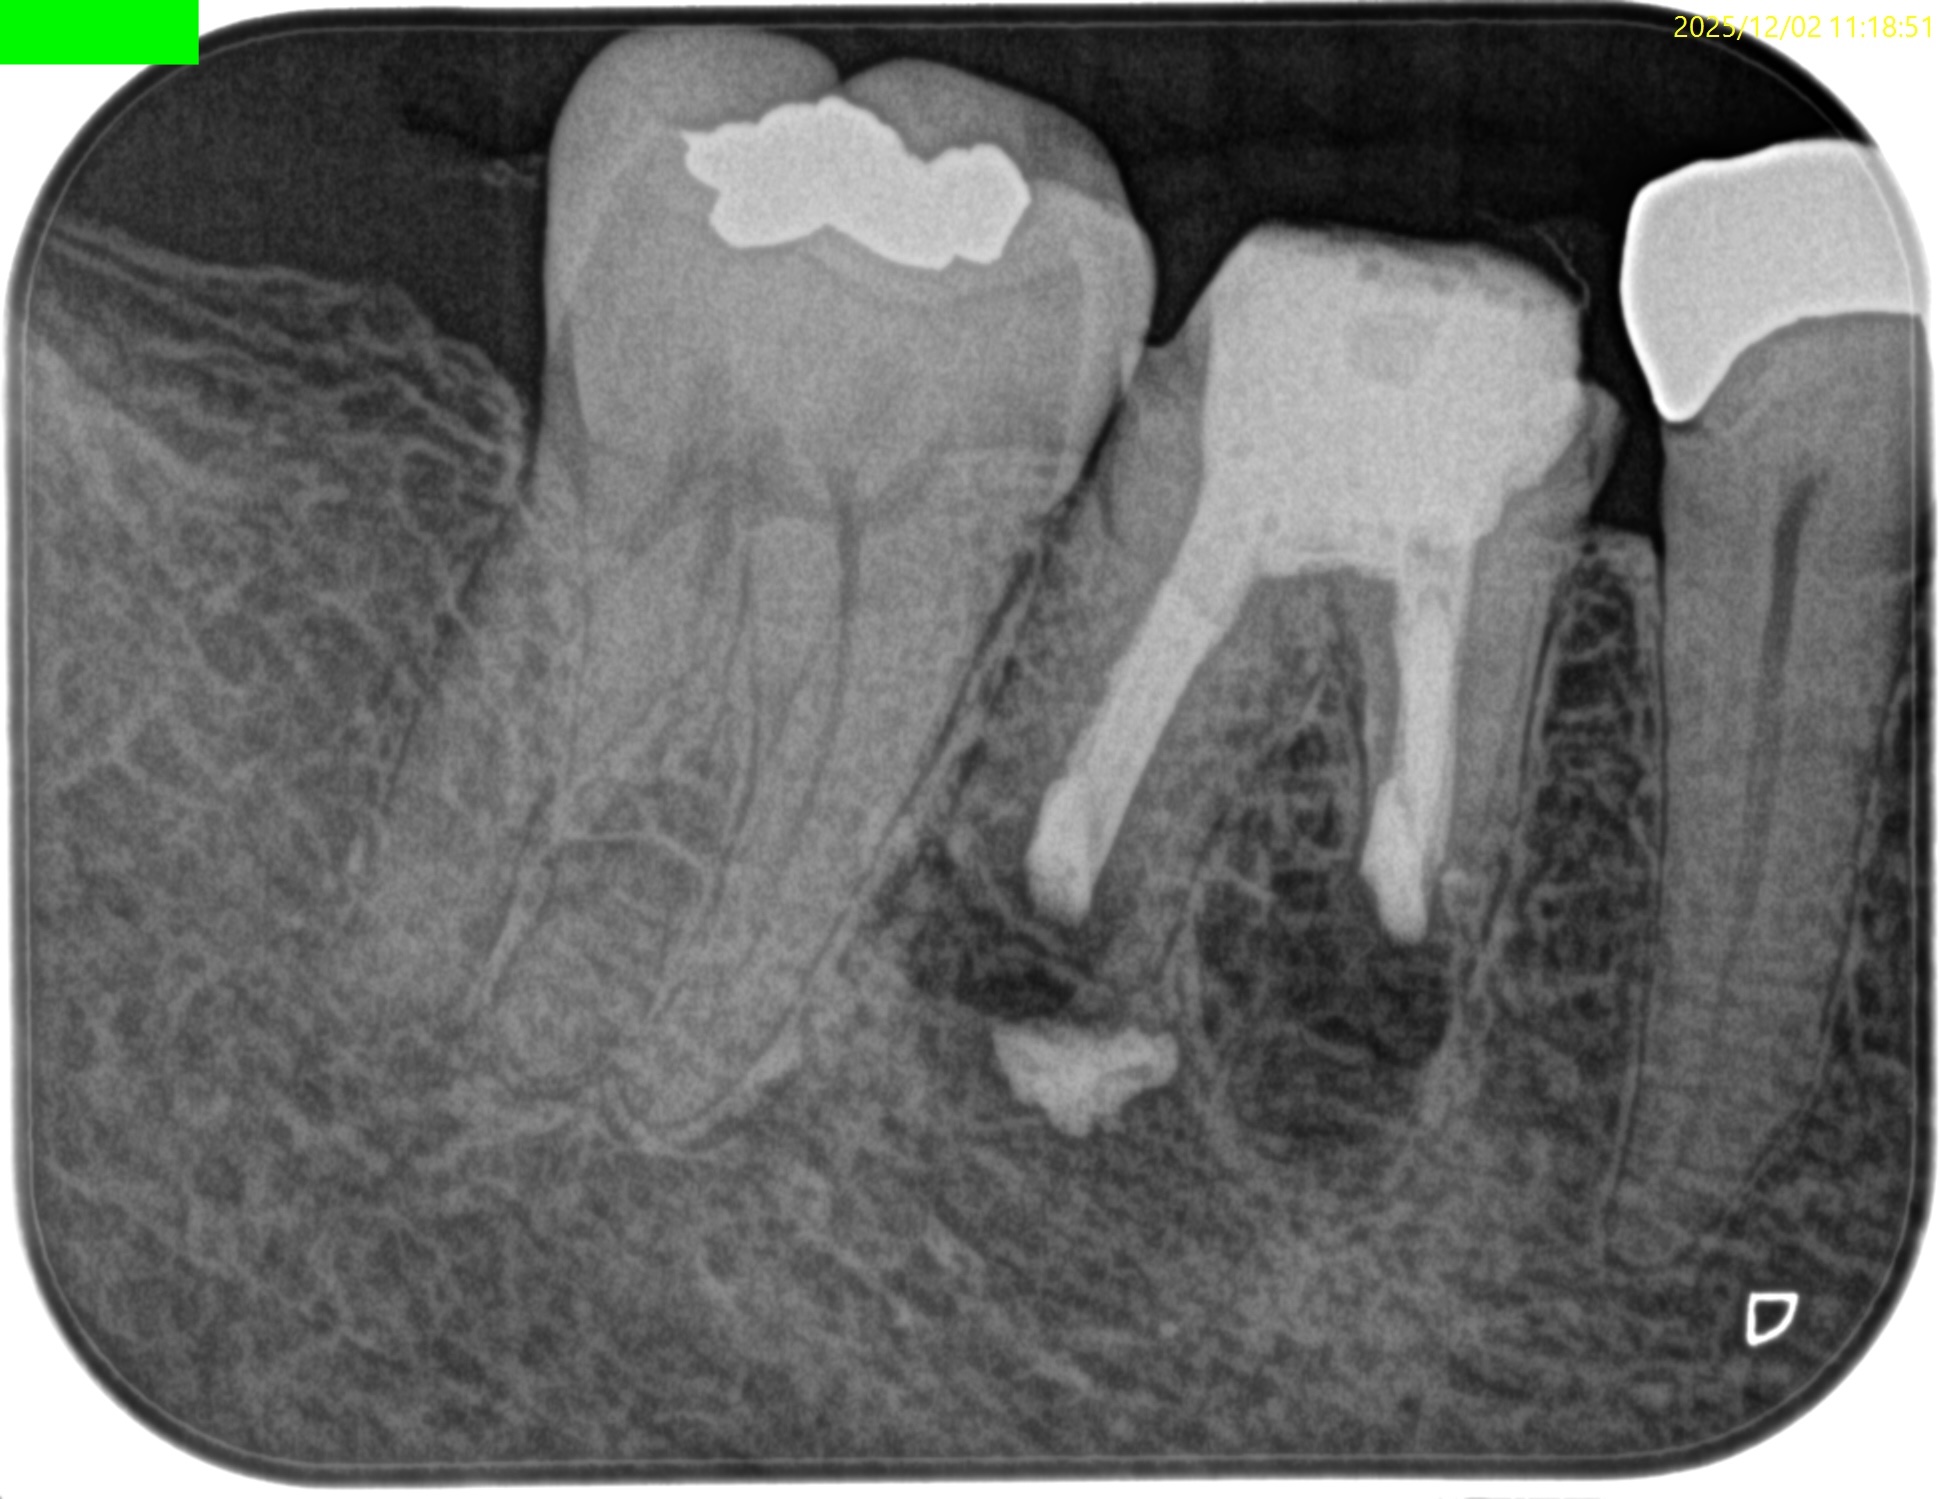

PA(2025.12.2)

#30 Cold N/A, Perc.(+), Palp.(+), BT(++), Perio Probe(WNL), Mobility(WNL)

#31 Cold+3/1, Perc.(-), Palp.(-), BT(-), Perio Probe(WNL), Mobility(WNL)

#30が患歯のようだ。